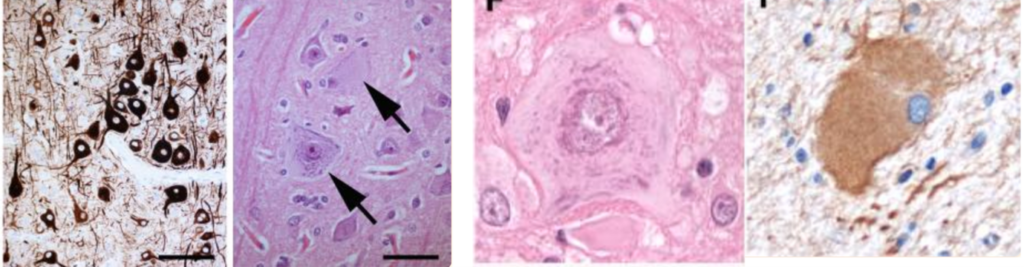

Figure 3 in turn zooms in on microscopic features of FCD II subtypes:

- FCD IIa: Dysmorphic neurons with abnormal neurofilament protein accumulation (SMI32).

- FCD IIb: Enlarged dysmorphic neurons with huge nuclei and abnormal Nissl aggregates; Balloon cells expressing vimentin, another hallmark of IIb.